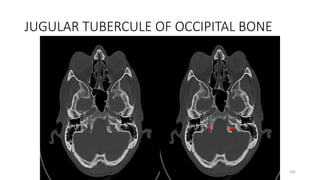

LEVEL-8

JUGULAR TUBERCULE OF OCCIPITAL BONE